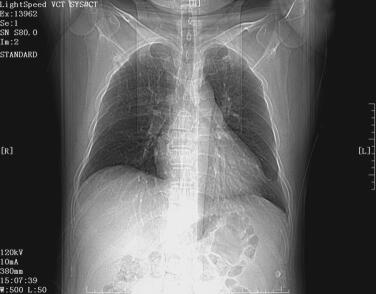

辅助检查:心电图示V1~V4导联呈QS波形,T波低平倒置;血常规示WBC 6.85×109/L,NEUT% 64%,NEUT 4.38×109/L,PLT 109×109/L,Hb 112g/L,RBC 4.87×1012/L;心肌酶谱未见明显异常(发病约18小时后);肾功能示BUN 15.02mmol/L、Scr 178μmol/L;血生化示Na+ 129mmol/L,K+ 5.65mmol/L,CO2-CP 16.4mmol/L,AG 21.15mmol/L;胸部X线(图1)示符合心力衰竭、急性肺水肿表现。

图1 胸部X线正位片示符合心力衰竭、急性肺水肿表现